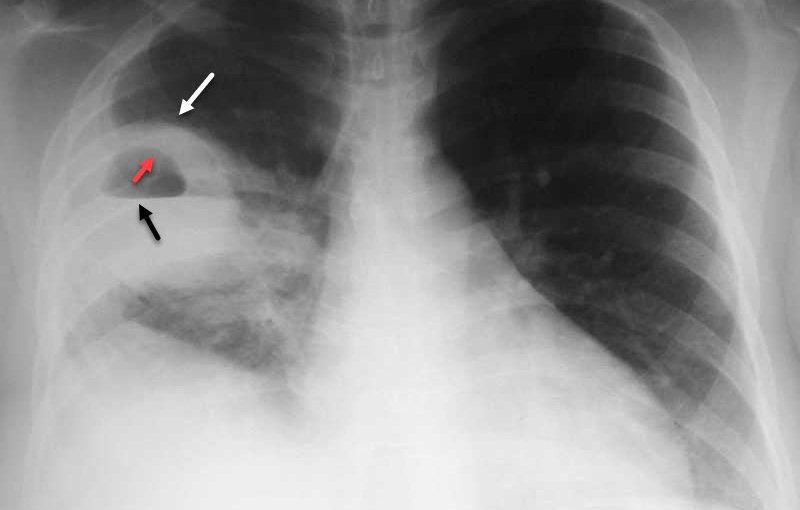

- Chụp X-quang kiểm tra viêm phổi.

Chụp X-quang giúp phát hiện ra virus RSV